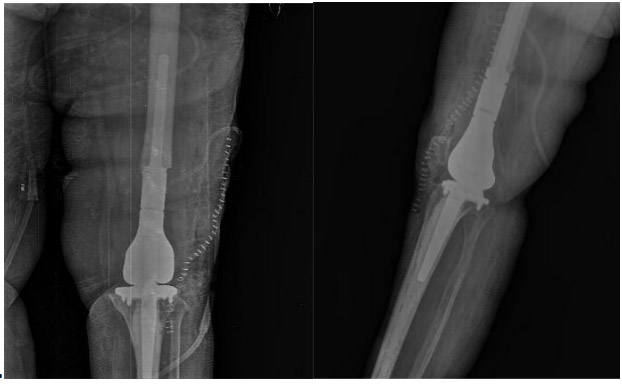

Post-surgery: The X-ray shows the implantation of a cemented distal femur tumor prosthesis.